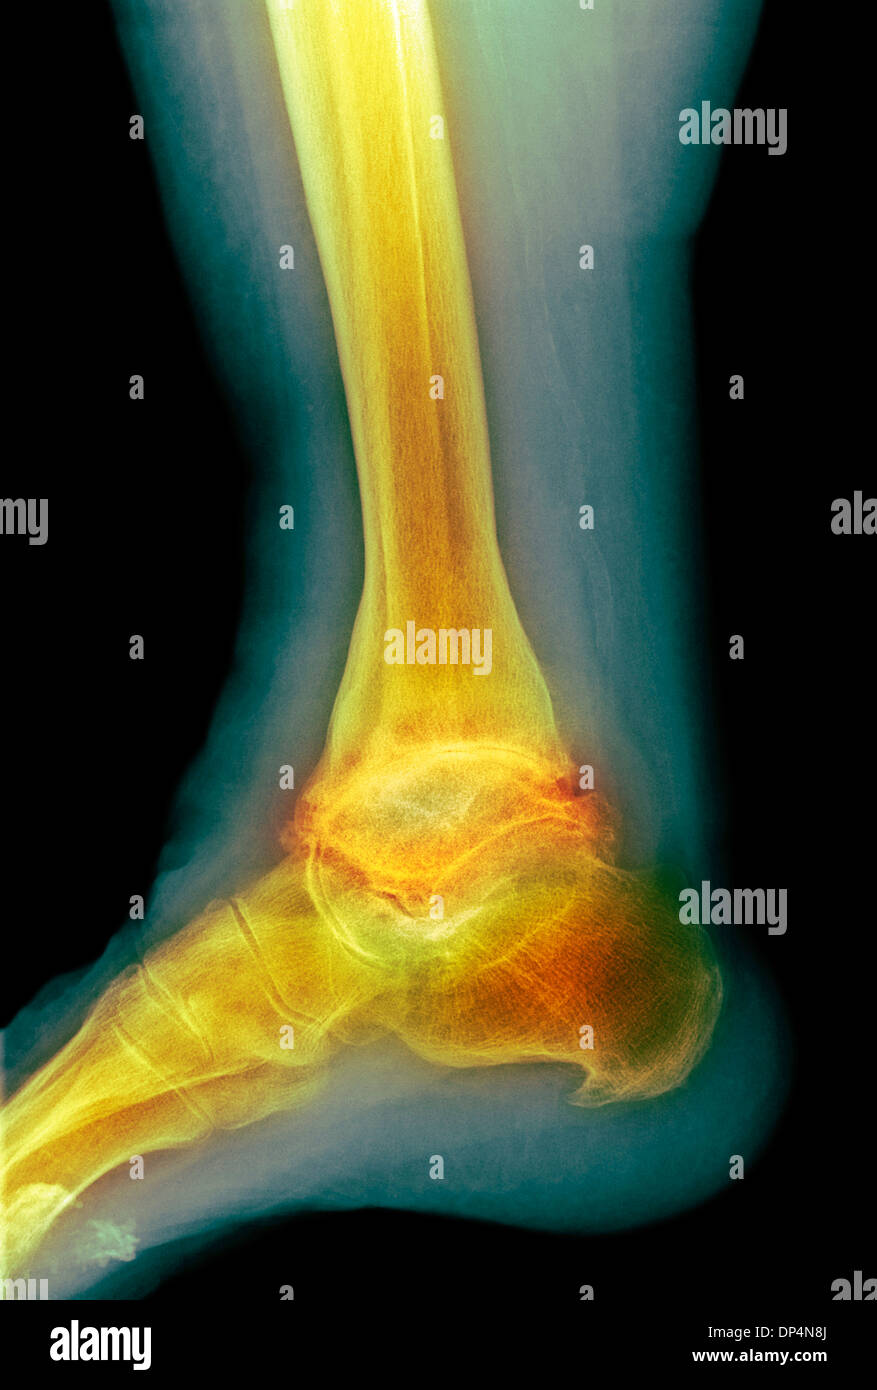

Severe osteoarthritis of the ankle Image Osteoarthritis Ankle Pain Arthritis in the ankle can lead to pain, swelling, deformity, and instability in the ankle joint. Ankle arthritis affects the tibiotalar. When you have ankle osteoarthritis, you might have inflammation or swelling of the joint that connects your foot with the lower part. Find out what other treatment options are out there from an orthopaedic surgeon. If you have ankle. Osteoarthritis Ankle Pain.

Osteoarthritis ankle x ray hires stock photography and images Alamy Osteoarthritis Ankle Pain Ankle arthritis affects the tibiotalar. Ankle arthritis is commonly caused by a prior ankle injury, such as an ankle fracture. Arthritis in the ankle can lead to pain, swelling, deformity, and instability in the ankle joint. When you have ankle osteoarthritis, you might have inflammation or swelling of the joint that connects your foot with the lower part. It’s common. Osteoarthritis Ankle Pain.

Ankle osteoarthritis, Xray Stock Image C053/3906 Science Photo Library Osteoarthritis Ankle Pain Visit a healthcare provider if you’re experiencing foot. Find out what other treatment options are out there from an orthopaedic surgeon. It’s common for arthritis to develop where any of the bones in your ankle meet. If you have ankle arthritis, it’s best to proceed with conservative management first. Other potential causes or risk factors include rheumatoid arthritis, joint infection. Osteoarthritis Ankle Pain.